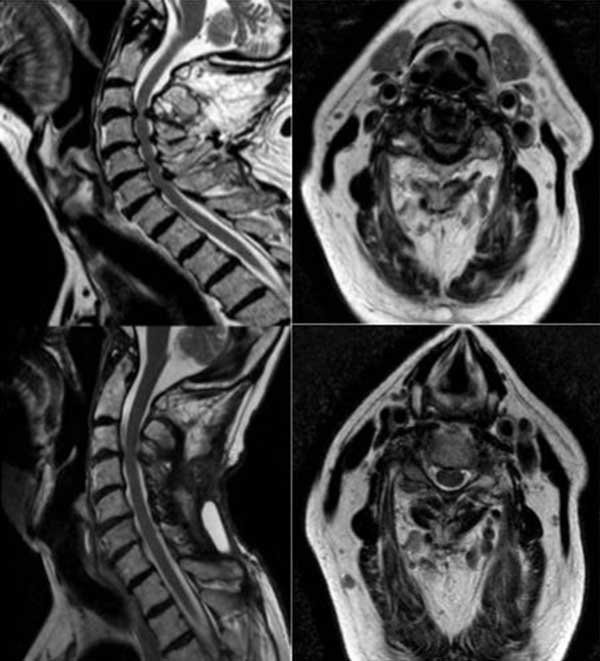

Paciente masculino de 72 años, con tetraparesia severa de instauración aguda secundario a latigazo cervical. Al examen físico: tetraparesia severa asociado a hipoestesia en 4 miembros a predominio de miembros inferiores y globo vesical. Nurick prequirúrgico de 5. En RM se observó una disminución del diámetro del canal cervical asociado a signos de edema medular (Figuras 8 y 9). Se propuso efectuar una laminoplastia entre los niveles C3-C7. No se evidenciaron cambios en la escala de Nurick.

Figura 8. Imágenes en corte sagital y axial de RM T2 cervical prequirúrgica (imagen superior izquierda y derecha) donde se observan múltiples osteofitos posteriores e hipertrofia facetaria con edema medular asociada y estrechamiento del canal espinal cervical a nivel C3-C7. Las imágenes posquirúrgicas (imagen inferior izquierda y derecha) evidencian la ampliación del canal espinal y descompresión medular.